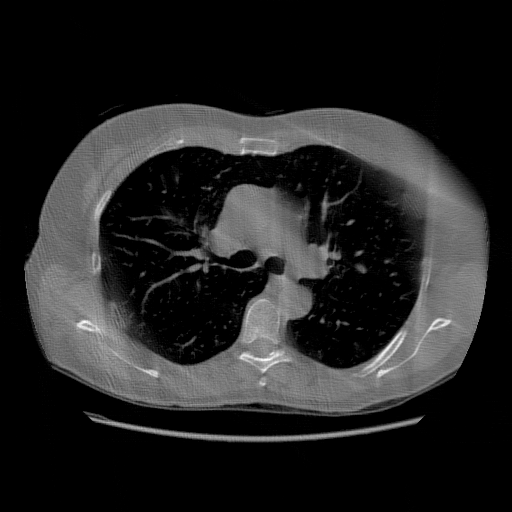

IV-C Few-View CT Reconstruction

In this section, the reconstruction performance of our proposed framework under few-view conditions will be tested. For the parallel and fan beam geometry, the number of views increases from to , uniformly distributing from to and to respectively. Such settings provide a complete benchmark of reconstruction performance, ranging from extremely sparse to relatively complete, full-view CT reconstruction. The experiment results are shown in Fig.5. Additionally, the ground truth, few-view ( views), and full-view ( views) CT reconstruction results of different methods are shown in the first and third rows of Fig.7 (parallel-beam, LIDC-IDRI dataset), and Fig.8 (fan-beam, LIDC-IDRI dataset).

IV-D Limited-Angle CT Reconstruction

To test the proposed framework’s performance on limited-angle reconstruction, we redo the experiment in the above section with the angular range changing from to for parallel-beam geometry and to for fan-beam geometry, one projection per degree. The experiment results are shown in Fig.6. Also, the ground truth and the limited-angle CT reconstruction results of different methods are shown in the row of Fig.7 (parallel-beam, LIDC-IDRI dataset), and Fig.8 (fan-beam, LIDC-IDRI dataset).

(a) Ground Truth

43.87dB/0.96

(b) ASD-POCS

47.96dB/0.97

(c) RBP-DIP

34.46dB/0.84

(d) DIP

26.63dB/0.93

(e) MED50

29.03dB/0.95

(f) RED-CNN

Conventional IR methods, even those with the help of regularizations such as total variation, are prone to artifacts when constrained by few-view and limited-angle conditions. However, as illustrated in the first and second rows of Fig.7b, and Fig.8b, these images still contain meaningful information which can be used to guide DIP related reconstruction methods, despite the presence of artifacts.

DIP related methods, which leverage the hierarchical structure of neural networks as a powerful prior, can better handle the aforementioned challenge. However, the original DIP method has its own limitations. It cannot generate detailed images or effectively enhance its accuracy as the number of measurements increases. For instance, in Fig.5a, the ASD-POCS algorithm achieves an approximate SNR gain of dB when the number of views increases from to , while the DIP method only attains an approximate dB gain. This problem is also shown in the last row of Fig.7, and Fig.8. Moreover, the DIP method may produce neural network specific artifacts, as shown in Fig.7d, Fig.8d, and Fig.12c. These artifacts are particularly problematic as they are often considered more undesirable than streak artifacts. Radiologists, with their professional experience, can interpret and account for streak artifacts, whereas network specific artifacts may prove more challenging to identify and address.

The proposed RBP-DIP framework combines the two approaches utilizing the newly devised RBP connection so that inherits the benefits of both methods. In Fig.4, the RBP-DIP method’s attainment of a 5dB SNR enhancement over the ASD-POCS method, despite exhibiting a larger loss. This implies that the improvement is not caused by the further minimization of the loss function but by the ability to choose a more reasonable reconstruction result from all candidates with similar losses. This is precisely the direct evidence of the successful combination of conventional IR and deep image prior in the proposed RBP-DIP framework. Subsequently, the improvement surpassing the original DIP method indicates the efficacy of the RBP connection. Moreover, by employing the RBP connection, neural network specific artifacts can be rectified effectively. As a result, substantial advancements can be shown in Fig.5, Fig.6, Fig.7, and Fig.8.

Also, Fig.5 and Fig.6, particularly Fig.6b, show that an increasing number of views does not sufficiently lead to improved performance of pre-trained models. The reason is that pre-trained models aim to learn the mapping between the input and the corresponding output from training datasets, rather than actually solve the corresponding inverse problem. Increasing the number of views cannot directly strengthen this mapping. Conversely, the proposed RBP-DIP directly minimizes the inconsistency between the ground truth and reconstructed images under the same measurements. Increasing the number of views reduces the dimensions of the solution space and thus benefits both network optimization and the iterative reconstruction (IR) algorithms integrated in the RBP connection. This outcome is further verified in the last row of Fig.7, and Fig.8, where RBP-DIP considerably outperforms other methods.